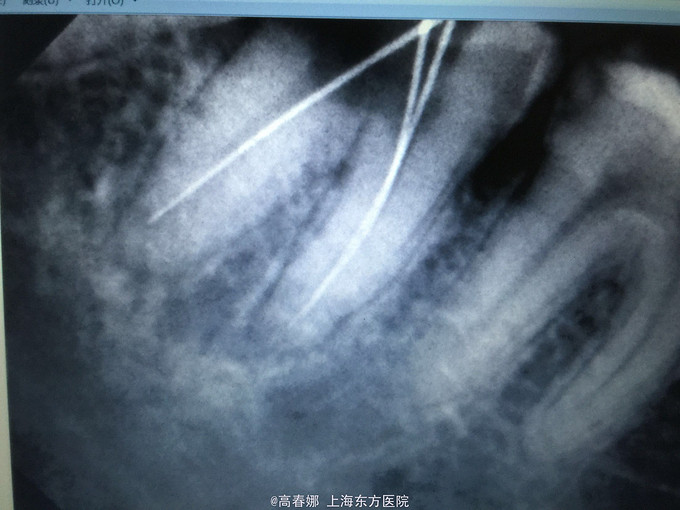

检查:47远中麟面龋坏,探诊(-),叩诊(+),松动I度,牙龈无明显红肿,牙周袋约3mm,冷诊(-)。 48近中阻生,未见明显龋坏,牙龈无红肿。 X线示:48近中阻生。47远中邻面龋坏及髓,根尖区低密度影像。

诊断:47慢性根尖周炎 48阻生齿(近中位) 治疗:48拔除后行47常规根管治疗后冠修复。